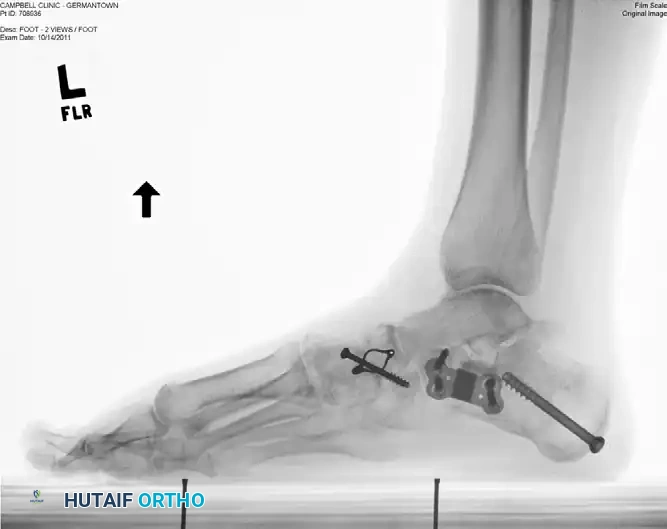

The following radiographs demonstrate a severe, decompensated flatfoot deformity treated with a comprehensive reconstruction, including lateral column lengthening with an allograft, a medial displacement calcaneal osteotomy (MDCO), and a naviculocuneiform (NC) arthrodesis to address fixed forefoot supination.

Figure 4: Anteroposterior (AP) radiograph demonstrating lateral column lengthening with a structural allograft secured by an H-plate, alongside a medial displacement calcaneal osteotomy and naviculocuneiform arthrodesis.

Figure 5: Lateral radiograph of the same patient, showing excellent restoration of the medial longitudinal arch, proper graft placement, and hardware integration.